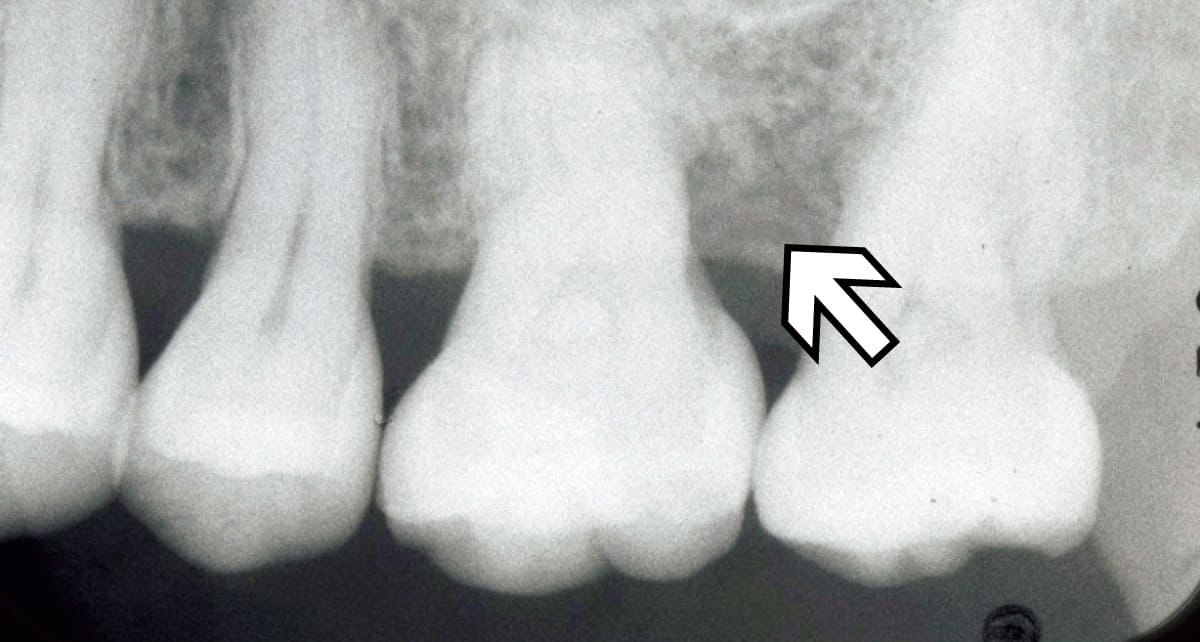

再生治療|失われた歯周組織を健康な状態に近づける。

Before

After

歯周病などでダメージを受けた歯周組織を再生させる治療。薬剤を使用して歯周組織の再生を促す方法や外科的治療を行うなど、さまざまな方法がある。歯ぐきを引き上げたり歯槽骨を再生させたりと歯の機能の改善にも役立つ。

【料金】15万円〜

【治療期間】3か月〜1年程度